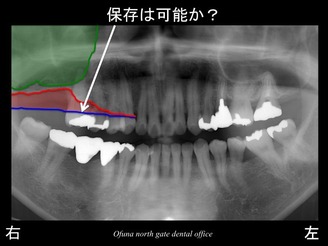

次に上顎洞です。

以下の緑線は上顎洞という空洞です。

緑線の内側は空洞なのです。

骨ではありません。

ただの 穴 です。

これも さらに分かりやすくするために、上顎洞 を緑色で表示します。

それでは、この上顎右側の奥歯は、治療が可能なのでしょうか?

抜歯しなくても保存可能なのでしょうか?

答えとしては、保存は可能です。

しかし、上顎右側の奥歯の骨吸収を 元の状態に回復させることは不可能です。